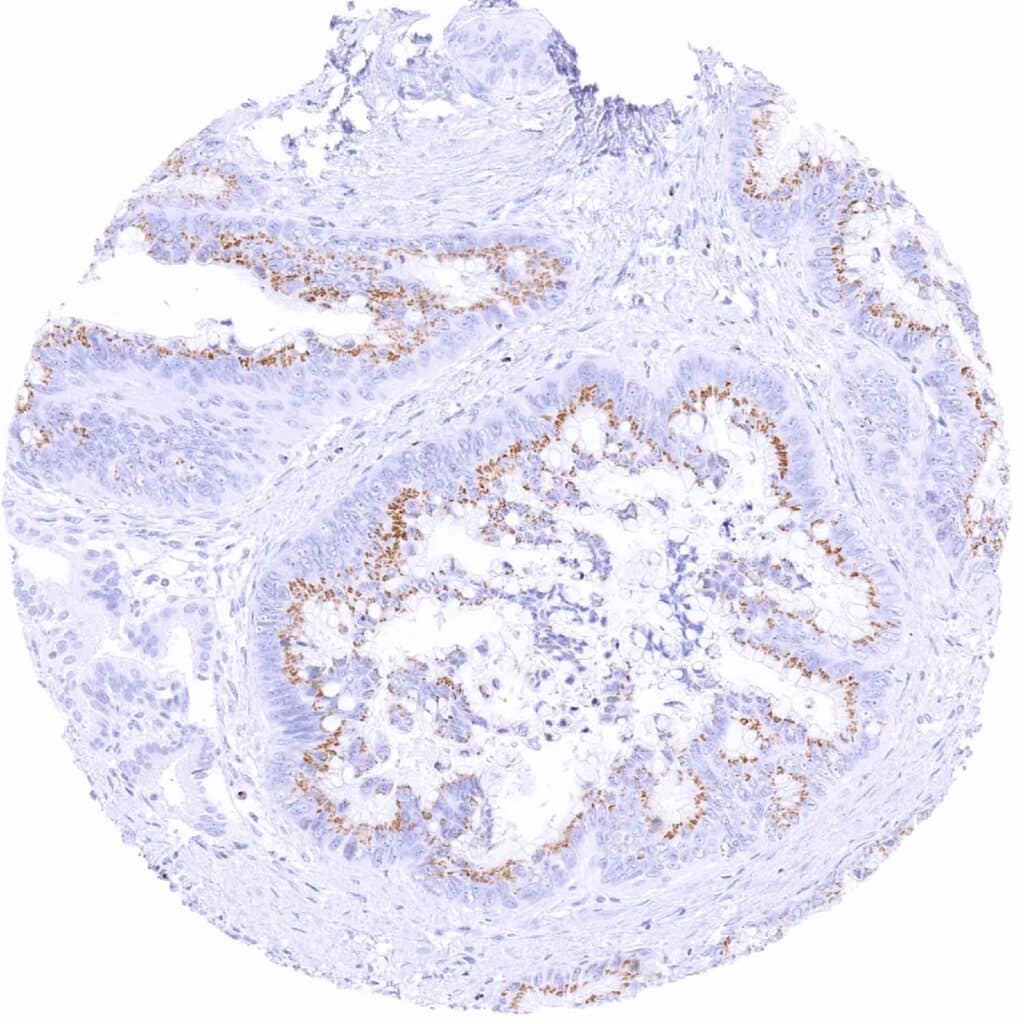

Pancreas – Ductal adenocarcinoma showing moderate granular perinuclear Prostein staining of neoplastic cells